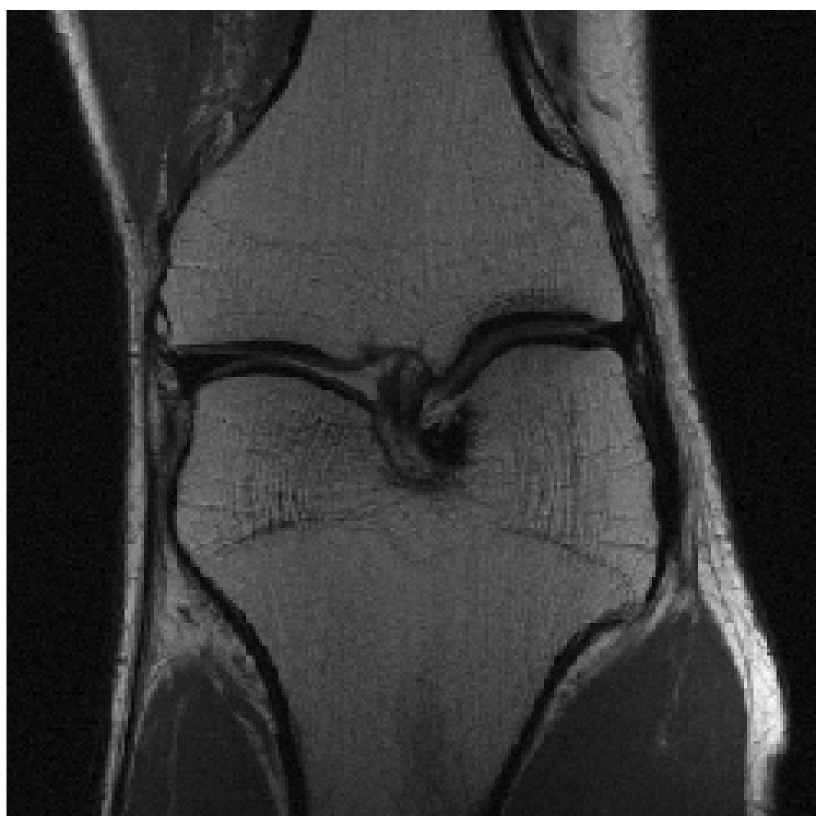

We evaluated our models on three data sets: the validation set as in Zbontar et al. (2018), and the test and challenge sets through the fastMRI website. A summary of these evaluations can be found in table 1111Results on the challenge data set will be added once publicly available.. To assess image quality more closely, we show some exemplary reconstructions from each model in figure 1.

(a) Multi-Coil RSS

Ground Truth

Refer to caption

(b) Multi-Coil 4-Fold

Reconstruction

(c) Multi-Coil 8-Fold

(d) Single-Coil ESC

(e) Single-Coil 4-Fold

(f) Single-Coil 8-Fold

Figure 1: Example reconstructions. The reconstructions visually improve the ground truth images, suggesting a strong prior.